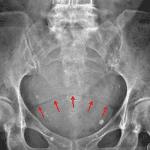

Age: 75

Sex: Female

Indication: Follow up renal stones

- Several calcific densities overlie the left renal outline with the largest measuring 10 x 4 mm at the junction of the upper pole and interpolar region

- Increased density in the anatomic pelvis draped over the urinary bladder

- Vascular calcifications